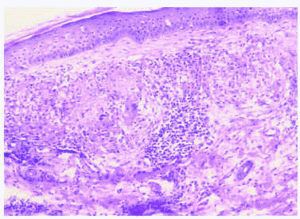

Se realizaron biopsias cutáneas de los 5 casos clínicos con tinciones para hematoxilina-eosina, mucina (hierro coloidal) y fibras elásticas (iodina de Verhoeff). En todos los casos se apreciaba una epidermis relativamente normal. En la dermis papilar y media presentaban un infiltrado inflamatorio granulomatoso denso y difuso, compuesto por células gigantes multinucleadas que contenían un material basófilo y algunos histiocitos acompañados a veces de linfocitos (figs. 3 y 4). En los casos 1, 3 y 4 se asociaban dichos cambios a un infiltrado inflamatorio compuesto por linfocitos pequeños, mientras que en el caso 2 este infiltrado inflamatorio era muy notable y en el caso 5 era escaso. No se apreciaban histiocitos «en empalizada» y las tinciones para mucina no mostraron cambios degenerativos en el colágeno ni incremento de mucina en las zonas con infiltrado granulomatoso. En las tinciones para fibras elásticas se apreciaban células gigantes multinucleadas que envolvían las fibras elásticas o con dichas fibras dentro de su citoplasma (fig. 5). En las áreas correspondientes al centro de la lesión anular, no se observaban fibras elásticas. En la parte más externa de la lesión cutánea se apreciaba elastosis actínica, con conglomerados de material basofílico en la dermis papilar.

Fig. 3.--Se aprecian granulomas que consisten en células gigantes multinucleadas e histiocitos intersticiales entre las fibras de colágeno amorfo y fragmentado. (Hematoxilina-eosina, x40.)

Fig. 4.--Detalle que muestra células gigantes fagocitando pequeñas fibras basofílicas en su citoplasma. (Hematoxilina-eosina, x100.)